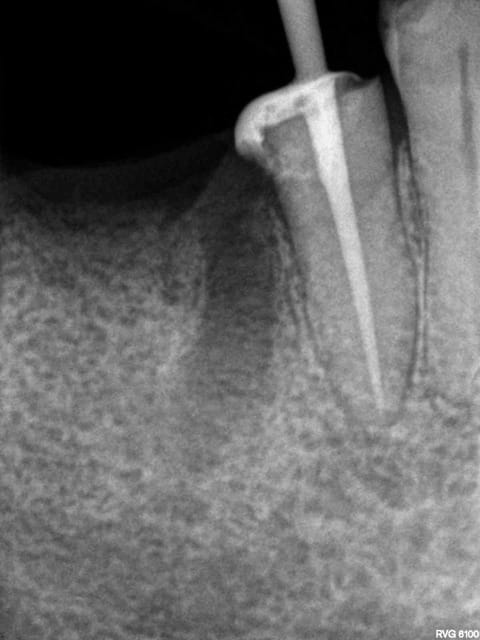

Exemple endo 45 taille empreinte. ( mac spaden) 35 mn.

Radio cone en place, cone scellé, mac spaden, logement tenon.

Manque de la place sur les trays zirc, ca serait bien d'en avoir des plus grands-)))))